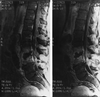

Lumbar vertebral osteomyelitis with mycotic abdominal aortic aneurysm caused by highly penicillin-resistant Streptococcus pneumoniae

We present a case of vertebral osteomyelitis with an adjacent abdominal aortic mycotic aneurysm caused by a highly penicillin-resistant Streptococcus pneumoniae strain. The occurrence of all three phenomena in a single patient has not been previously described. This presentation offers the opportunity to reflect on the increasing incidence of S. pneumoniae as a resistant pathogen, the treatment of highly penicillin-resistant S. pneumoniae, and the etiologic agents of both vertebral osteomyelitis and mycotic aneurysm.